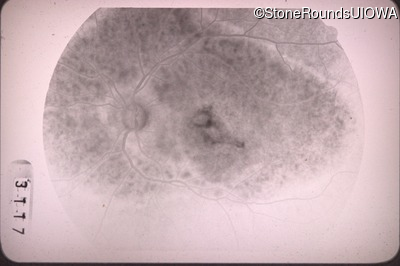

Fluorescein Angiography - Right - 20/100 -1

Exemplar

Fluorescein Angiography - Left - 20/40 -1